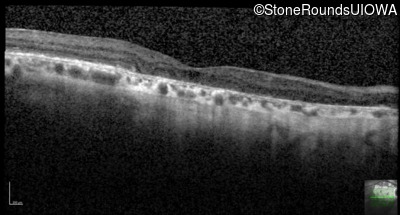

Highlighted Images

Age at visit: 55 years

OD OS